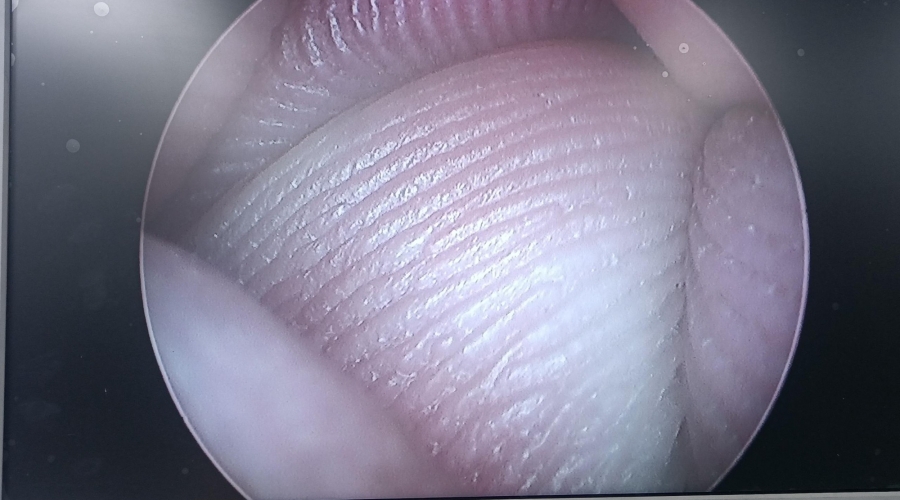

設(shè)備型號(hào)Wolf狼牌電切鏡8650.414

故障內(nèi)容圖像模糊,棒透鏡破碎,導(dǎo)光錐破碎,目鏡罩破碎,鏡身有磕碰,但不影響使用。

維修方案更換棒透鏡、導(dǎo)光錐、目鏡罩,校對(duì)圖像,內(nèi)窺鏡抗震蕩抗沖擊性能測(cè)試,內(nèi)窺鏡密封性性能檢測(cè);內(nèi)窺鏡抗震蕩性能測(cè)試,內(nèi)窺鏡冷熱沖擊性能檢測(cè)。